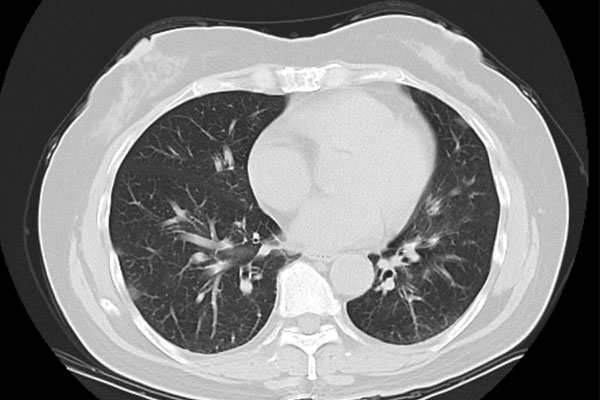

“Chúng tôi mới đi du lịch một tuần trước. Sau khi trở về, tôi bắt đầu xuất hiện các triệu chứng sốt, ho, đau họng và đau nhức cơ thể. Tôi đã chịu đựng triệu chứng này trong vài ngày nhưng đến hôm kia, do không thể tiếp tục chịu đựng nên tôi đã nhanh chóng đến bệnh viện địa phương để chụp X-quang lồng ngực. Các bác sĩ cho biết tôi bị biến chứng viêm phổi và khuyên nên nhập viện ngay” - Cô Lý (50 tuổi, đã thay đổi tên) lấy tờ báo cáo chụp X-quang có dòng chữ “viêm phổi góc dưới bên trái” với các vết trắng phổi cho hay.

Kết quả xét nghiệm cho thấy, cô Lý cùng gia đình đều dương tính với virus cúm A và riêng cô Lý đã biến chứng viêm phổi. Sau 2 ngày điều trị, thân nhiệt của cô Lý đã trở lại bình thường và các triệu chứng như ho, đau họng cũng cải thiện đáng kể.